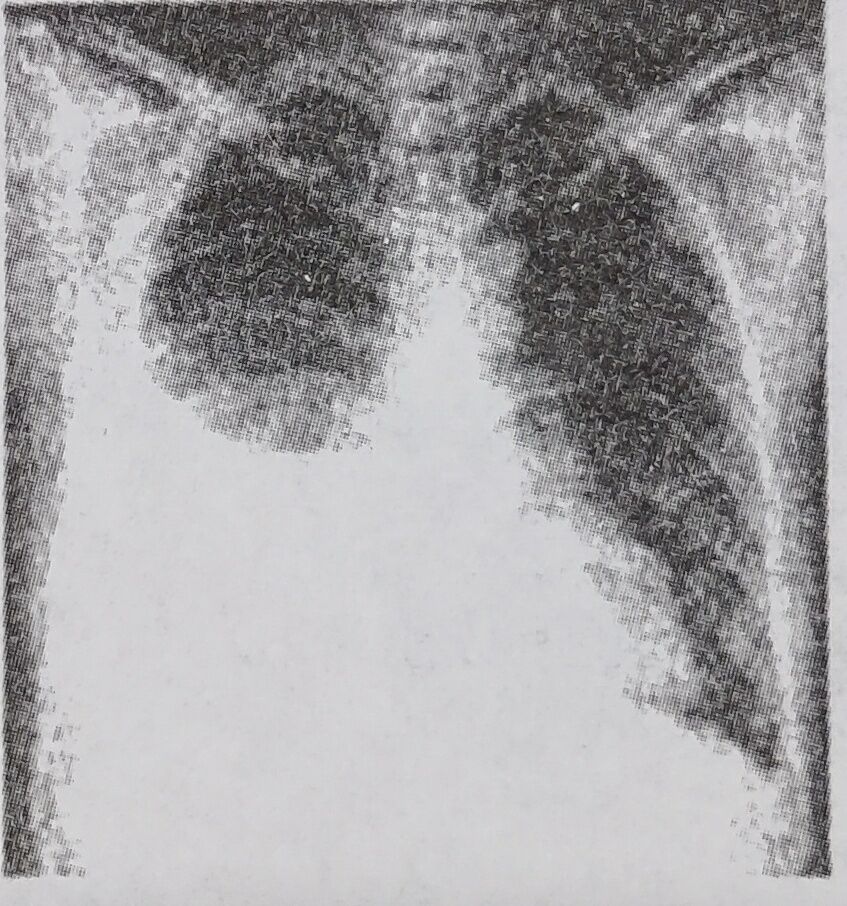

【题干】男性,30岁。发热、咳嗽伴右侧胸痛10天,喜右侧卧位。胸片如下,首先考虑的诊断是()

A.右侧气胸

B.右侧胸腔积液

C.右侧肺癌

D.右侧肺炎

E.右侧肺脓肿

【参考答案】B